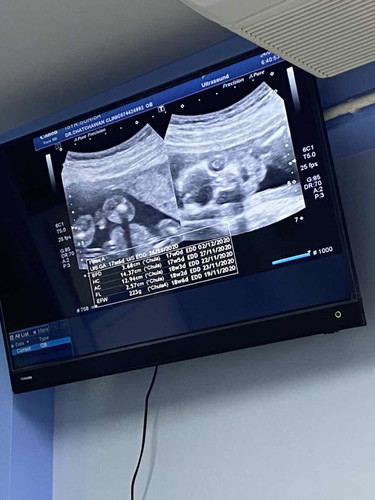

18w6d น้ำหนักน้อง 223g ใช่มั้ยค่ะ ตามเกณฑ์ไหม หรือน้ำหนักน้องน้อยไป